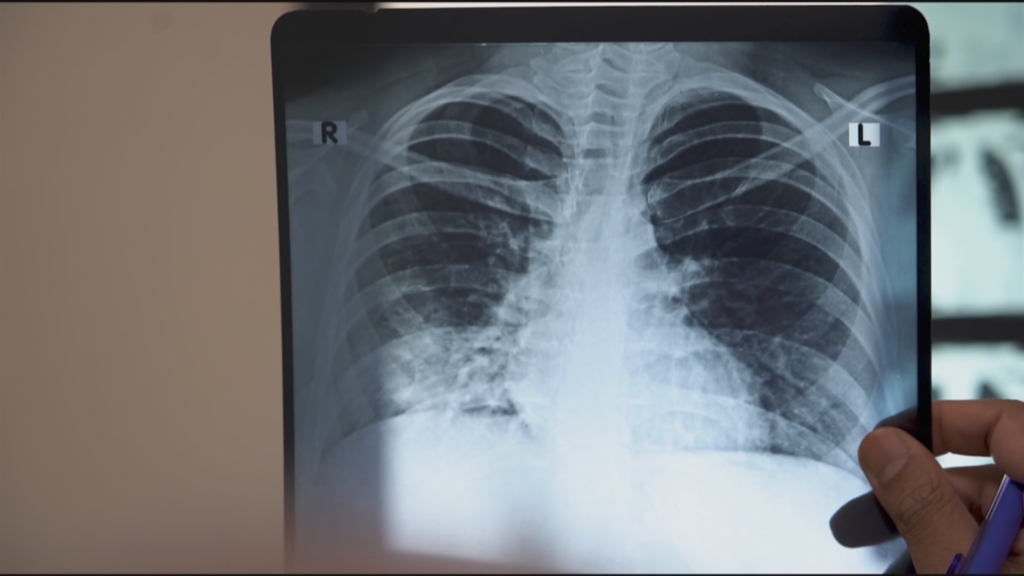

In 2018, Indian Prime Minister Narendra Modi promised to eradicate tuberculosis (TB) in the country by 2025, aiming to set an example globally. Since December 2024, India’s health minister has led a “100-day campaign” to eliminate TB, but recent WHO data shows India is far from its goal. It recorded 2.5 to 3 million new cases and over 400,000 deaths in 2023 alone, accounting for a third of global TB cases and deaths. The country faces two major issues: TB treatment shortages and the rise of multi-drug-resistant TB. While treatments exist, the government’s slow approval of their distribution has hindered progress, leaving India at a critical juncture in its fight against the disease. FRANCE 24’s Khansa Juned and Alban Alvarez report.